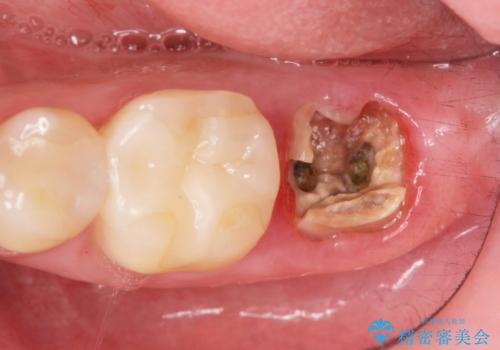

- 「歯から異臭がする。」とのことで相談に来院されました。

X線検査を行ったところ、セラミッククラウン下に虫歯が再発し、歯の破折も認めました。